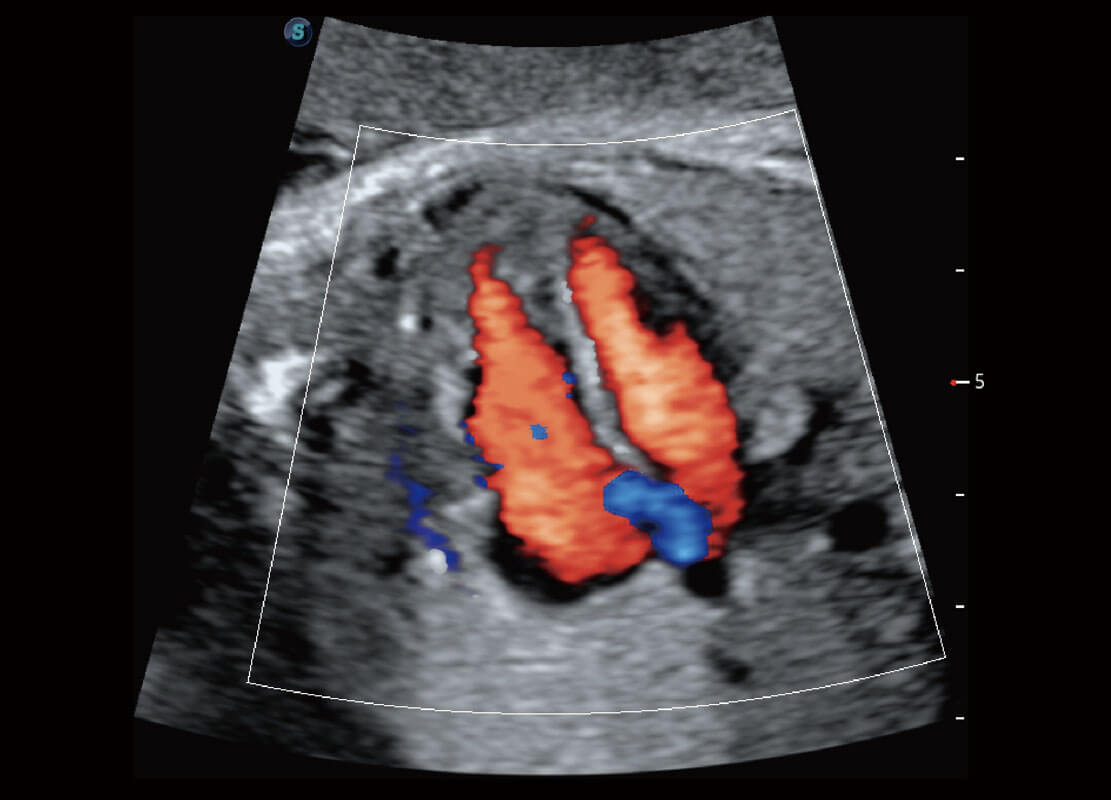

腔内妇科-宫腔分离

腔内妇科-卵巢